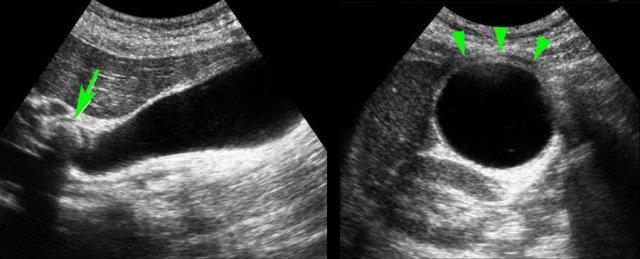

Hình ảnh siêu âm của một bệnh nhân bị phình to túi mật cấp tính, được khảo sát trên mặt phẳng dọc và mặt phẳng ngang.

Sỏi gây tắc nghẽn đang ở trạng thái kẹt (mũi tên).

Lưu ý rằng khi ấn đè, túi mật phình to phồng lên về phía thành bụng (đầu mũi tên), cho thấy áp lực trong lòng túi mật tăng cao.